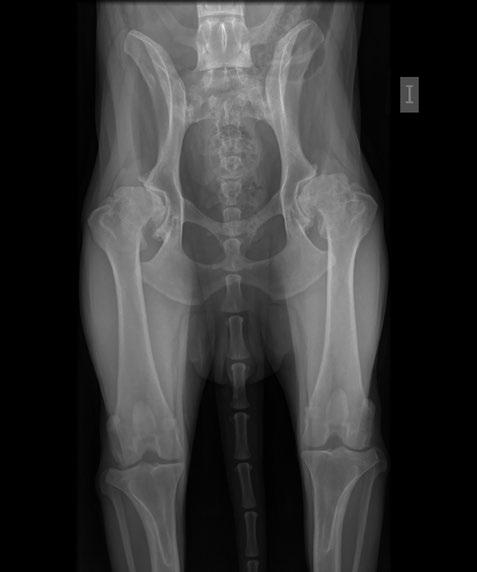

Issuu converts static files into: digital portfolios, online yearbooks, online catalogs, digital photo albums and more. Sign up and create your flipbook.